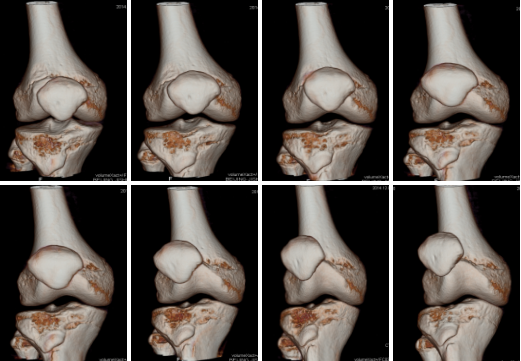

病例二 男,16歲, 右側(cè)髕骨脫位。

膝關(guān)節(jié)屈曲運(yùn)動(dòng)過(guò)程中的開(kāi)始、中間和結(jié)束的橫軸位圖像顯示:右髕骨相對(duì)股骨髁部出現(xiàn)明顯外移和外翻。

膝關(guān)節(jié)屈曲運(yùn)動(dòng)過(guò)程中, 連 續(xù) 的 V R 圖 像 顯 示: 右髕骨脫離 股骨滑車, 出現(xiàn) 持續(xù)的外移和外 翻, 髕骨旋轉(zhuǎn)改 變不明顯。

該病例采用不動(dòng)床的掃描方式對(duì)膝關(guān)節(jié)屈曲運(yùn)動(dòng)進(jìn)行連續(xù)動(dòng)態(tài)掃描,這種技術(shù)可以對(duì)于一些靜態(tài)圖像顯示正常,但卻有臨床活動(dòng)性病變指征的疾病進(jìn)行動(dòng)態(tài)掃描,對(duì)這些疾病治療前的評(píng)估診斷具有重要的意義。